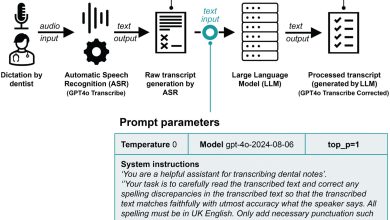

As ferramentas de fala de IA podem revolucionar a manutenção de registros odontológicos – mas é preciso cautela

Representação esquemática do pipeline de transcrição de 2 estágios. Crédito: Jornal de pesquisa odontológica (2025). DOI: 10.1177/00220345251382452 Um novo estudo…